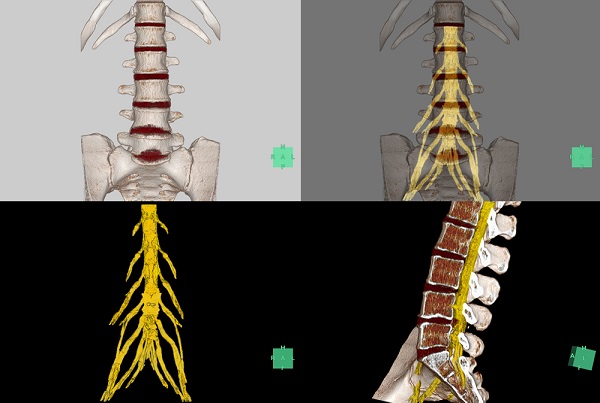

(2)MRI腰神経抽出機能

MRIの画像から自動で腰神経のみを抽出でき、CTの骨画像とMRIの腰神経をフュージョンすることで、骨と神経の位置関係が確認できる。

例えば腰椎すべり症の手術においては、骨と神経の位置関係を把握し適切な手術方法の選択に役立てることができる。